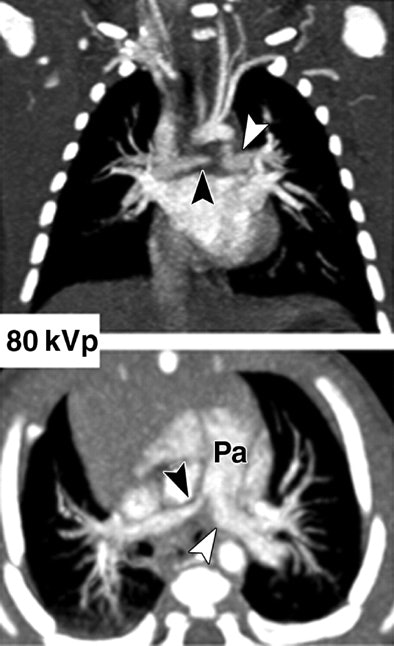

| Images show three different examples of congenital vascular abnormalities of chest evaluated with 64-slice CT with use of automatic tube current modulation. Oblique coronal maximum intensity projection images (upper row, above) and transverse section images (lower row, above) of patients scanned at 80 kVp and 100 kVp. Image set A (above) shows stenotic pulmonary artery (black arrowheads) in 6-month-old girl. Note difference in vessel caliber between right and left pulmonary arteries (white arrowhead). Image set B (below) shows left lower pulmonary vein (llPv) draining (black arrows) in right (rA) instead of left (lA) atrium in 2-year-old boy. ulPv = upper left pulmonary vein, rV = right ventricle, and lV = left ventricle. Image set C (100 mAs, bottom) shows tetralogy of Fallot with large septal defect (white arrows), overriding ascending aorta (aA), and stenotic pulmonary artery (Pa) in 6-month-old boy. |